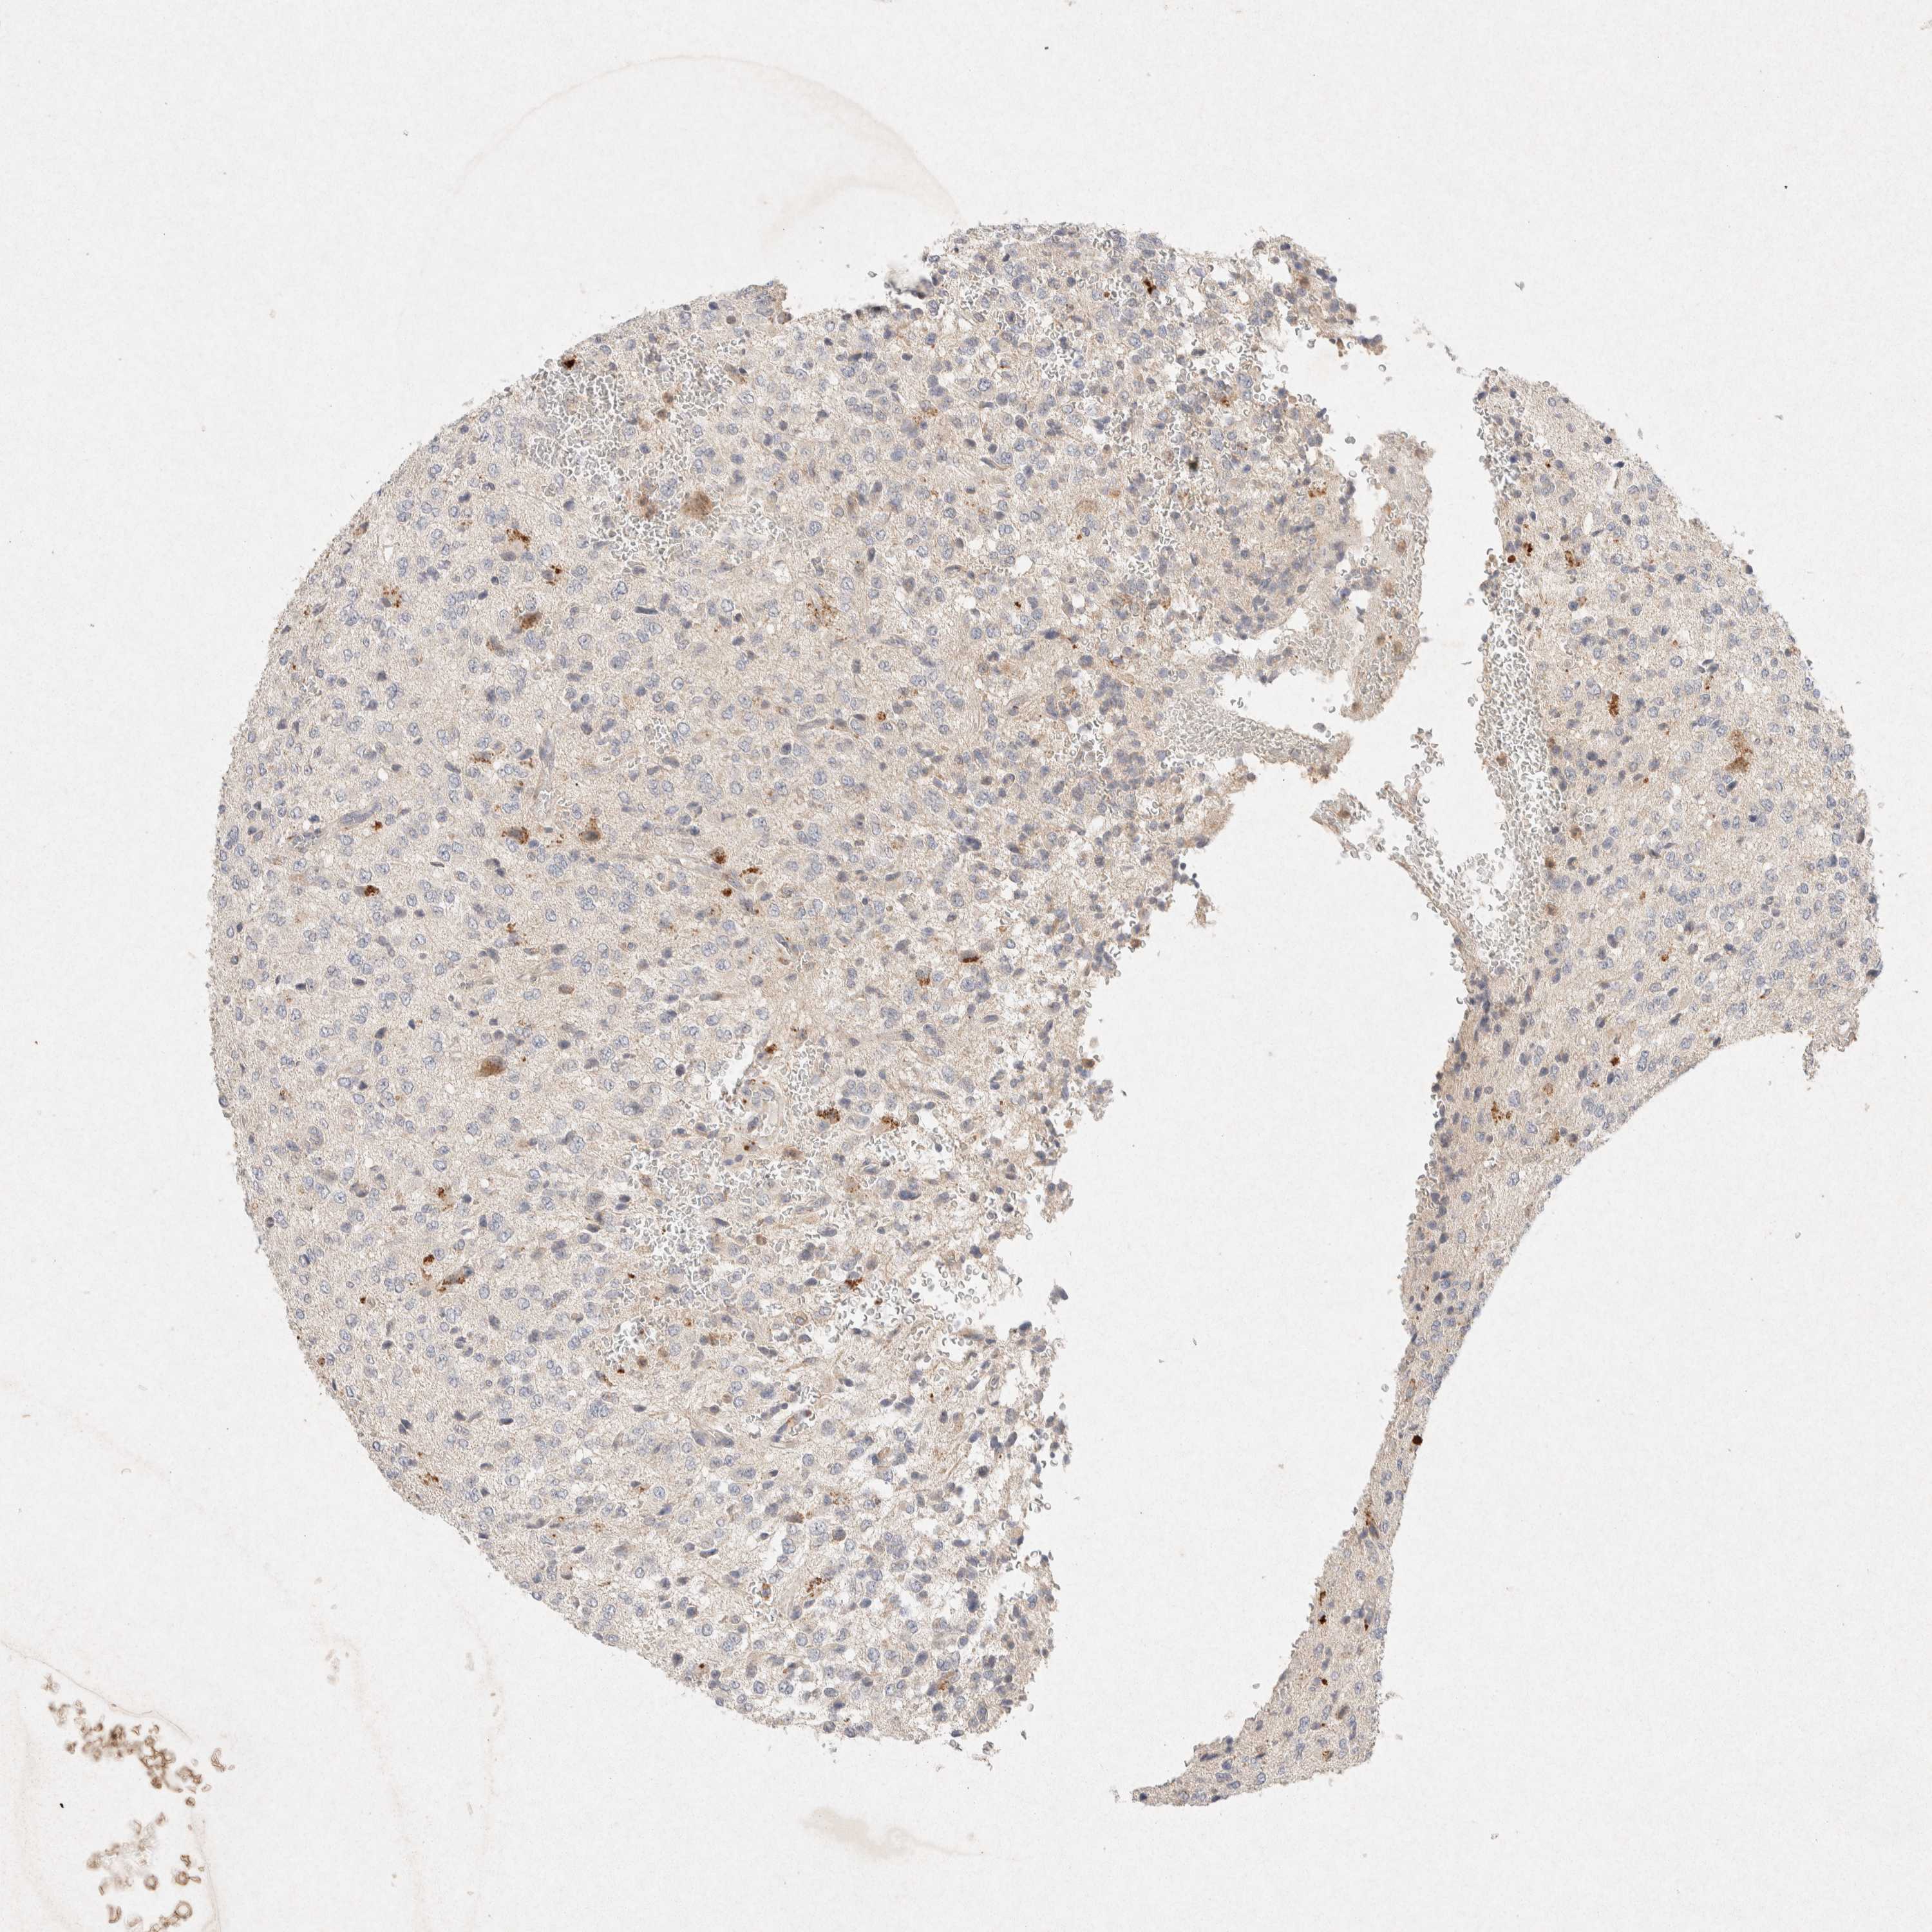

GLIOMA - Protein expressioni

A mouse-over function shows sample information and annotation data. Click on an image to view it in a full screen mode. Samples can be filtered based on level of antibody staining by selecting one or several of the following categories: high, medium, low and not detected. The assay and annotation is described here.

Note that samples used for immunohistochemistry by the Human Protein Atlas do not correspond to samples in the TCGA dataset.

Antibody stainingi

Antibody staining in the annotated cell types in the current human tissue is reported as not detected, low, medium, or high, based on conventional immunohistochemistry profiling in selected tissues. This score is based on the combination of the staining intensity and fraction of stained cells.

Each image is clickable and will lead to virtual microscopy that enables deeper exploration of all samples and also displays staining intensity scores, fraction scores and subcellular localization as well as patient and tissue information for each sample.

Antibody HPA042141

Antibody CAB022449

Staining

High

Medium

Low

Not detected

Intensity

Strong

Moderate

Weak

Negative

Quantity

>75%

75%-25%

<25%

None

Location

Nuclear

Cytoplasmic/membranous

Cytoplasmic/membranous,nuclear

Glioma, malignant, High grade

Glioma, malignant, Low grade